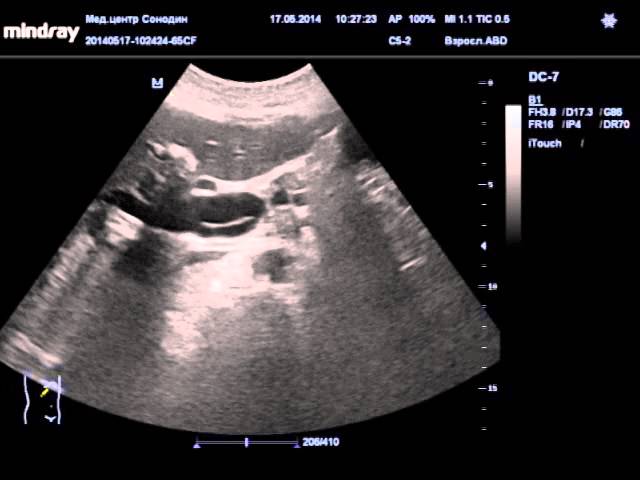

Смотрите в видео наглядно, как на мониторе выглядит гепатобилиарная система: